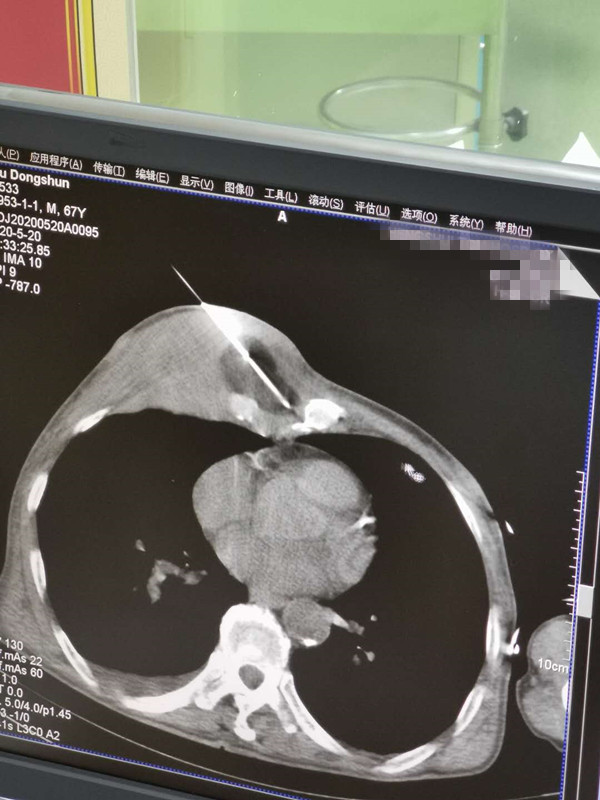

67岁胸部肉瘤氩氦刀冷冻消融

发布人:美国氩氦刀技术官方网站    发布时间:2020/5/21 14:53:37